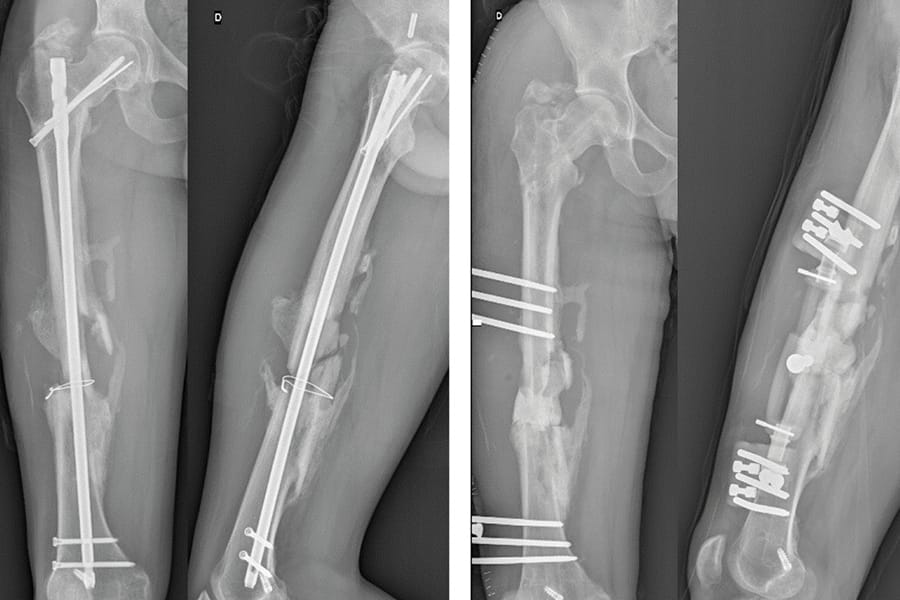

Technique Pseudarthrose du fémur ou du tibia : prise de greffe avec le système RIA sur l’os pseudarthrose , Marie Le Baron Hôpital Nord, APHM, Chemin des Bourrely 13000 Marseille, France 🖂 marie.lebaron@ap-hm.fr , Pascal Maman Hôpital Nord, APHM, Chemin des Bourrely 13000 Marseille, France , Richard Volpi Hôpital Nord, APHM, Chemin des Bourrely 13000 Marseille, France , Xavier Flecher Hôpital Sainte Marguerite, Université Aix-Marseille II, Marseille, France N°338 - Novembre 2024 ● 19 min de lecture